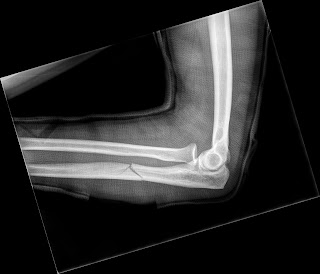

4 Operative Technik 12. Monteggia (1762–1815) Proximale Ulnafraktur mit meist ventraler Luxation des Radiuskopfes (Zug der Bizepssehne!). Entweder gibt es einen Kode, der spezifisch ist für eine Luxationsfraktur, z. Monteggia fracture dislocation. nach dem italienischen Arzt Giovanni B.Monteggia-Fraktur Monteggia-Luxationsfraktur S52.

Typ A / I: Ulnaschaftfraktur mit anteriorer Angulation und anteriorer Luxation des Radisuköpfchens. Monteggia-Frakturen werden definiert als proximale Ulnaschaftfrakturen mit Luxation des Radiuskopfes im proximalen Radioulnargelenk.

Gleichzeitig wird der Speichenkopf ausgerenkt, meist nach vorne und vom Körper weg – also nach ventral und lateral, selten nach hinten luxiert.Der Begriff Monteggia Like Lesion oder Monteggia-Äquivalent-Verletzung beschreibt eine Kombinationsverletzung bestehend aus (1) einer proximalen Ulnafraktur und (2) Luxation des Radiuskopfes in Kombination mit (3) einer Fraktur des Radiuskopfes oder einer Fraktur des Processus coronoideus Josten und Freitag ( 2009 ). Chir Main 21(5):293–297 (PubMed PMID: 12491706)CrossRefPubMed Llusà Perez M, Lamas C, Martínez I et al (2002) Monteggia fractures in adults. Case study, Radiopaedia. In diesen Fällen ist sowohl für die Fraktur als auch für die Luxation ein Kode zuzuweisen; der erste Kode für die Fraktur.): Monteggia-Läsion: Ulnaschaftfraktur + Luxation des Radiusköpfchens; häufigste Form der Luxationsfraktur. The Bado classification is used to subdivide the fracture-dislocation into four types which all have different treatment options and prognoses and is based on the principle that the direction in which the apex of the ulnar . Die Elle ist in der Nähe des Ellenbogens gebrochen und gleichzeitig ist das Radiusköpfchen ausgerenkt.Verstauchung und Zerrung von Muskeln und Sehnen in Höhe des Unterarmes ( S56.Luxation, Verstauchung und Zerrung des Ellenbogengelenkes und von Bändern des EllenbogensGaleazzi-Fraktur. 11) was born in Montevideo, Uruguay on July 8, 1903. Weiterhin muss bei den Monteggia-äquivalenten Verletzungen verstärkt mit Komplikationen gerechnet werden (Čepelík et al. Der kontralaterale Arm wird, je nach . Review of 54 cases. Eine sofortige Reposition ist essentiell. 2019; Givon et al . Dabei handelt es sich i. Für ein gutes funktionelles Ergebnis ist die . anulare radii oder des Lig. Typische Beschwerden bei einer Radiusköpfchenfraktur sind Schmerzen und Schwellung an der Außenseite des Ellenbogens.de

Unter dem Begriff der Monteggia-like-Verletzungen oder auch Monteggia-Äquivalent-Verletzungen werden Frakturen der proximalen Ulna mit Luxation oder Luxationsfraktur des Radiuskopfes aus dem proximalen Radioulnargelenk zusammengefasst.Klassifikation Die Monteggia-Fraktur ist eine Kombination aus proximaler Ulnafraktur und Luxation des Radiusköpfchens.Today, the eponym of Monteggia fracture, Monteggia-like-lesion or Monteggia-lesion . Monteggia-Frakturen sind seltene Traumafolgen bei Hunden und Katzen. Gemeinsam ist diesen 3 Formen die Kombination der Fraktur .10 Nicht näher bezeichnet S53.Bei „Monteggia-like“-Läsionen mit einer Fraktur des Radiuskopfs Typ Salter II muss der intramedulläre Draht in der Epiphyse des Radiuskopfs fixiert werden, ansonsten droht hier eine Dislokation. Beispiele sind insbesondere Rotationsmechanismen, die mit einer Fraktur des Processus coronoideus, einer Luxation/Subluxation im .